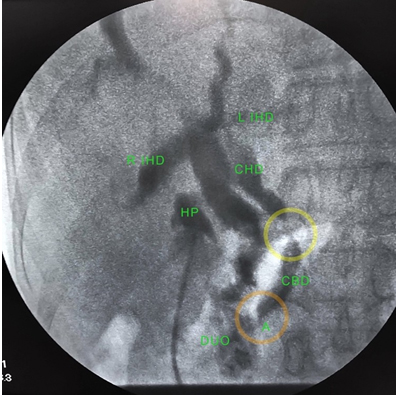

The patient was started on ceftriaxone and metronidazole along with intravenous antispasmodic and analgesics. The patient was admitted to an indeterminate ward in relative isolation while awaiting swab results. The patient was scheduled for open cholecystectomy, intraoperative cholangiography with possible CBD exploration. A COVID-19 PCR test was performed and came out negative for COVID-19 after seven days. The patient during the interim remained afebrile with normal vital signs and tolerable abdominal pain. The leukocytosis reverted to normal after four days of antibiotics. The patient underwent surgery at the non-COVID operating room. Anesthesia was administered using combined epidural and general anesthesia. Intubation was performed in an aerosol box as a precaution against aerosol production. The surgical team comprised of a senior biliary surgeon assisted by two senior residents. All were in level 4 personal protective equipment (PPE) as per recommendation for pandemic surgery during that time. A Kocher incision was used and revealed a markedly distended gallbladder with thickened walls, with dense adhesions noted in the Hartmann’s pouch and hepatoduodenal area. Careful dissection was unable to clearly identify the triangle of Calot. The team proceeded with gallbladder decompression evacuating white bile. The gallbladder was opened longitudinally for intraluminal extraction of a 3.5 × 3 cm pigment stone impacted in the Hartmann’s pouch, exposing the bile duct with yellow bile coming out (Figure 3). A French 16 Foley catheter was used to introduce contrast material with the balloon inflated in the Hartmann’s pouch and cholecystocholangiography was performed using fluoroscopy (C-arm). The intraoperative cholangiography revealed the following: dilated proximal hepatic duct, significant narrowing at the mid common bile duct, normal distal bile duct, tapering at the ampulla, and egress of dye into the duodenum (Figure 4). The team proceeded with cholecystectomy. Leaving a part of the Hartmann’s pouch intact on the lateral CBD wall. The remaining gallbladder wall was used as a flap to cover the exposed common bile duct, completing a choledochoplasty (Figure 5). The total operating time was 2.5 hours with blood loss of 200 cc. The postoperative diagnosis was obstructive jaundice from Mirizzi syndrome Type II. The final specimen is shown in Figure 6. There were no noted perioperative complications and the patient was discharged two days after surgery. Follow-up was done with the surgical team through teleconsultation. Sutures were removed after 10 days in a local health center by a general practitioner. All symptoms referable to the gallbladder disease resolved on latest follow-up two months after the surgery.

Figure 4: Intraoperative cholangiography. Left. This is the intraoperative cholangiography (IOC) of the patient. The Foley catheter balloon was inflated in the Hartmann’s pouch (HP). The cystic duct was obliterated. The intrahepatic ducts (IHD), and common hepatic duct (CHD) were dilated. The common bile duct (CBD) had narrowing (yellow circle) and the distal end was not dilated. There egress of dye to the duodenum (DUO). There was noted tapering on the ampulla (A) (orange circle).

As detailed above, despite lack of access to diagnostics and therapeutic endoscopy the patient successfully underwent definitive surgery. The surgical team was composed of the most experienced residents along with the attending surgeon to expedite the operation and limit unnecessary exposure to both the patient and the surgical team. This was in preparation for the anticipated technical difficult attendant to MS and the need for accurate intraoperative decision. The radiology department likewise made sure that a technician well versed in the use of the C-arm fluoroscopy was there to assist, instead of the team relying on static cholangiography. In regular days, intraoperative cholangiography for biliary surgeries in PGH were done with static portable X-rays requiring development of films in a separate facility due to resource limitations. This is reflected on the average operating time of cholecystectomy with intraoperative cholangiography in PGH which is approximately 3 hours 40 minutes [17]. A portable fluoroscopy (Figure 4) intraoperative cholangiography was utilized to have a real time assessment of the biliary tree. It provided faster, and more efficient visualization of the surgical field, thus promoting a safer surgery to prevent bile duct injuries [18],[19],[20].